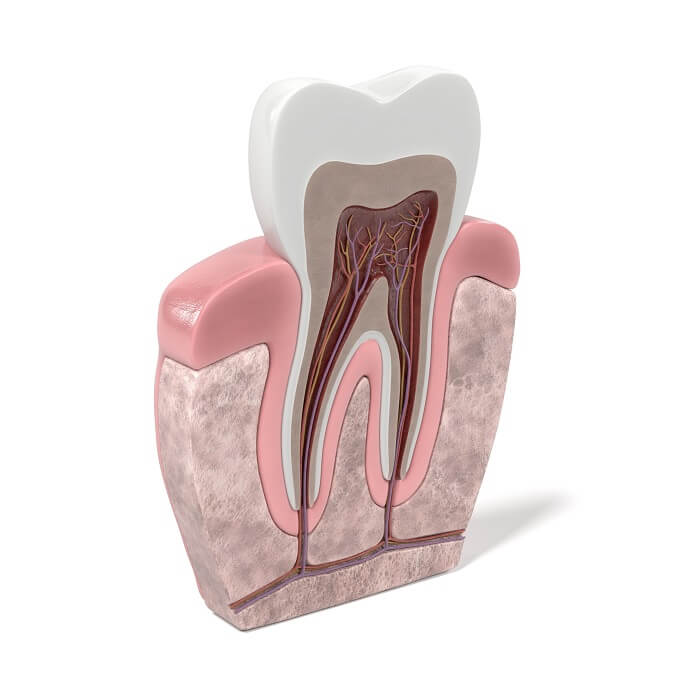

A classificação de Vertucci é um dos tantos modelos que buscam classificar a anatomia do sistema de canais radiculares. Ela foi criada em 1984 com o objetivo de enquadrar os tipos anatômicos dentais internos.

Se você já frequenta as suas primeiras aulas de endo, é bem provável que esteja começando a estudar essa classificação, que é fundamental para compreender a existência de diferentes tipos de canais articulares. Além disso, é importante destacar que muitos profissionais não têm sucesso nos procedimentos pela falta de conhecimento sobre as variações anatômicas dessa área.

Em 1974, Frank J. Vertucci apresentou um artigo sobre um estudo realizado com 300 dentes e, a partir dessa observação, propôs a classificação de sistema de canais radiculares dividida em quatro tipos, mas focada na anatomia interna dos dentes anteriores. Dez anos depois, o dentista trouxe novas informações que complementaram as da década anterior.

Nesta nova proposta, a classificação está mais completa e é organizada em oito tipos. De todas as pesquisas feitas sobre o assunto, a de Vertucci é a mais utilizada atualmente e considerada a “estandarte de ouro”.